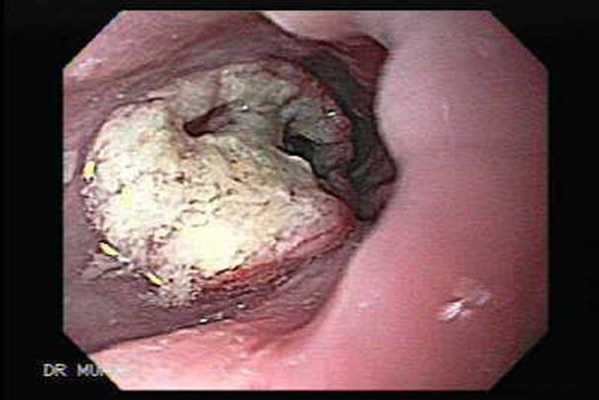

- Первое исследование — эндоскопия пищевода (ЭГДС) с биопсией опухоли.

• Эндоскопическое исследование пищевода – Эзофагогастродуоденоскопия (ЭГДС). Обычно, во время процедуры сразу исследуются пищевод, желудок и двенадцатиперстная кишка. Во время исследования под местной анестезией через рот вводится эндоскоп, который далее проводится в глотку, пищевод, желудок, двенадцатиперстную кишку и позволяет осмотреть внутреннюю поверхность перечисленных органов. Эндоскоп представляет собой тонкий гибкий шланг с подсветкой и камерой на конце, для получения видеоизображения. Изображение передается на противоположный конец эндоскопа и просматривается через глазок либо на мониторе. Кроме того, эндоскоп имеет приспособление для взятия кусочков ткани под визуальным контролем для последующего исследования полученных образцов под микроскопом. Эндоскопическое исследование, в настоящее время, является единственным методом, позволяющим выявлять рак пищевода на самых ранних, бессимптомных, стадиях.

• Биопсия – забор образцов ткани для последующего исследования их под микроскопом. При раке пищевода биопсия, обычно, производится во время эзофагоскопии. Последующее исследование под микроскопом проводится врачем-патоморфологом и позволяет определить наличие рака, его разновидность, а также выявить в пищеводе изменения предшествующие развитию рака.

Рентгенодиагностика рака пищевода

Эндоскопическая картина аденокарциномы

Эндоскопическая картина плоскоклеточного рака